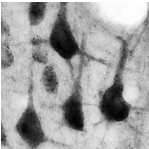

Canavan disease